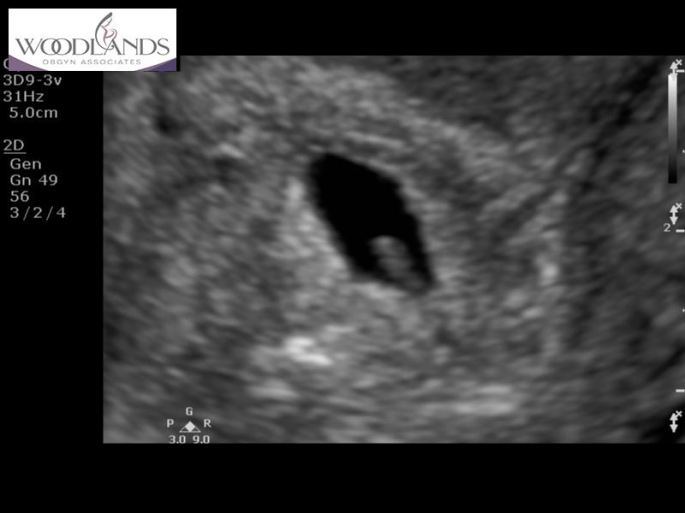

oh.my.gosh. There it was. A little bean. HR and all. Coming in at 114bpm. Amazing to have a heart beat that soon. I was only registered 5w,4d. They kept thinking 7 weeks but I insisted that the date of conception does not go on that projected date and they finally listened. We see this little RAINBOW again on Monday, September 23rd. Stay tuned. I’m praying it’s still there. Still beating will all of Gods amazing force and glory. And…didn’t multiply. Haha!!!